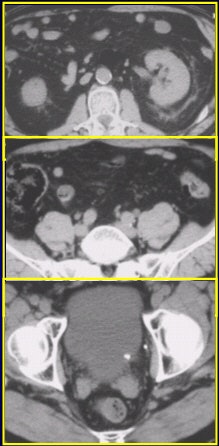

![]() |

On 120 mAs (above) and 240 mAs (below), an extraurinary diagnosis of right hemorrhagic ovarian cysts and abdominal aortic aneurysm. Images courtesy of Dr. James Bell.